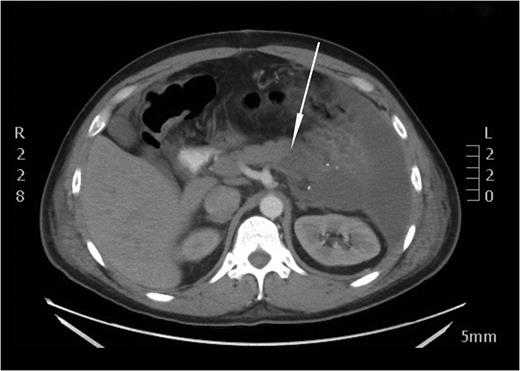

After the secondary survey, the patient was subjected to a computed tomography (CT) study, which showed a Grade IV splenic injury per the American Association for the Surgery of Trauma injury grading score with contrast extravasation (Fig. 1), a lower lobe contusion of the left lung, fractures of the IV and VI–XI ribs on the left side and bilateral iliac wing fractures. The pancreatic parenchyma was well perfused and homogenous in a portal venous phase CT-imaging (Fig. 2).

Axial view of the initial CT scan depicting a normally perfused pancreatic tissue.